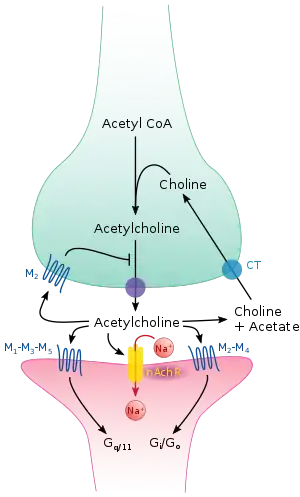

Acetylcholine is synthesized in certain neurons by the enzyme choline acetyltransferase from the compounds choline and acetyl-CoA. Cholinergic neurons are capable of producing ACh. An example of a central cholinergic area is the nucleus basalis of Meynert in the basal forebrain.[8][9] The enzyme acetylcholinesterase converts acetylcholine into the inactive metabolites choline and acetate. This enzyme is abundant in the synaptic cleft, and its role in rapidly clearing free acetylcholine from the synapse is essential for proper muscle function. Certain neurotoxins work by inhibiting acetylcholinesterase, thus leading to excess acetylcholine at the neuromuscular junction, causing paralysis of the muscles needed for breathing and stopping the beating of the heart.

Like many other biologically active substances, acetylcholine exerts its effects by binding to and activating receptors located on the surface of cells. There are two main classes of acetylcholine receptor, nicotinic and muscarinic. They are named for chemicals that can selectively activate each type of receptor without activating the other: muscarine is a compound found in the mushroom Amanita muscaria; nicotine is found in tobacco.

Nicotinic acetylcholine receptors are ligand-gated ion channels permeable to sodium, potassium, and calcium ions. In other words, they are ion channels embedded in cell membranes, capable of switching from a closed to an open state when acetylcholine binds to them; in the open state they allow ions to pass through. Nicotinic receptors come in two main types, known as muscle-type and neuronal-type. The muscle-type can be selectively blocked by curare, the neuronal-type by hexamethonium. The main location of muscle-type receptors is on muscle cells, as described in more detail below. Neuronal-type receptors are located in autonomic ganglia (both sympathetic and parasympathetic), and in the central nervous system.

Muscarinic acetylcholine receptors have a more complex mechanism, and affect target cells over a longer time frame. In mammals, five subtypes of muscarinic receptors have been identified, labeled M1 through M5. All of them function as G protein-coupled receptors, meaning that they exert their effects via a second messenger system. The M1, M3, and M5 subtypes are Gq-coupled; they increase intracellular levels of IP3 and calcium by activating phospholipase C. Their effect on target cells is usually excitatory. The M2 and M4 subtypes are Gi/Go-coupled; they decrease intracellular levels of cAMP by inhibiting adenylate cyclase. Their effect on target cells is usually inhibitory. Muscarinic acetylcholine receptors are found in both the central nervous system and the peripheral nervous system of the heart, lungs, upper gastrointestinal tract, and sweat glands.

When a motor neuron generates an action potential, it travels rapidly along the nerve until it reaches the neuromuscular junction, where it initiates an electrochemical process that causes acetylcholine to be released into the space between the presynaptic terminal and the muscle fiber. The acetylcholine molecules then bind to nicotinic ion-channel receptors on the muscle cell membrane, causing the ion channels to open. Sodium ions then flow into the muscle cell, initiating a sequence of steps that finally produce muscle contraction.